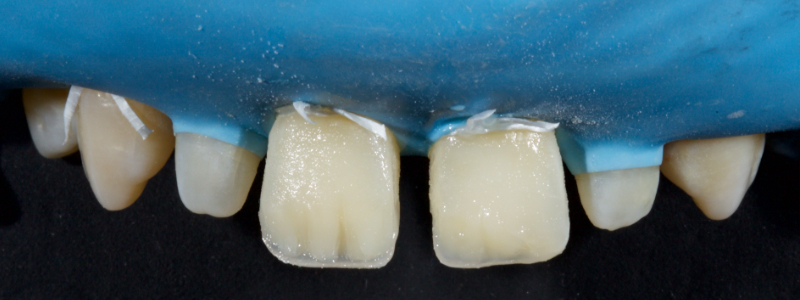

Before polymerization, the contact points are cleared with an Interproximal Carver Long (IPCL) like American Eagle (Fig. 9). The resin mass is then polymerized to create a palatal shell (Fig. 10).

Inferiorly, the dentin resin mass should not be placed apical to the superior aspect of the infinity bevel since that would result in a visible opaque line in the final restoration. The dentin mass should be under contoured (Figs. 14 and 15).